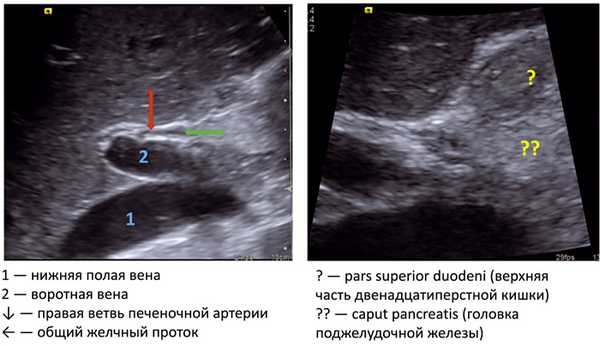

Стенки крупных и мелких протоков на рис. 5 неровные, это выявляется только в случае обструкции. Общий желчный проток располагается за пределами печени, на рис. 4 он изогнут, примыкает к висцеральной поверхности печени, правый его участок внедряется в головку поджелудочной железы [7].

Рис. 4. Общий желчный проток.

На рис. 4 видны также дополнительные ориентиры: крупный венозный сосуд — нижняя полая вена, кзади от которой располагаются правая почечная артерия, правая ветвь печеночной артерии и воротная вена. Диаметр общего желчного протока в норме

На рис. 5 области в желтом круге на эхограммах соответствуют области в желтом круге на схеме [11]. Самой поверхностной структурой является общий печеночный проток, глубже под прямым углом его пересекает правая печеночная артерия, еще глубже располагается воротная вена. В норме воротная вена (около 6 мм) толще, чем общий печеночный проток (около 4 мм). На схеме и на эхограмме в красном круге область, в которой пузырный проток соединяется с общим печеночным протоком — место образования общего желчного протока.

На рис. 6 на эхограмме 1 видна голова «Микки Мауса»: в воротах печени — уши (правое — общий желчный проток или в некоторых случаях общий печеночный проток, левое — собственная печеночная артерия), голова — воротная вена, туловище — нижняя полая вена. Желтым цветом показана супрадуоденальная часть общего желчного протока на эхограмме и на схеме [12].

На эхограмме 2 (см. рис. 6) определяется воротная вена, параллельно ей общий желчный проток (видна супрадуоденальная и ретродуоденальная части), верхняя часть двенадцатиперстной кишки, привратник, поджелудочная железа.